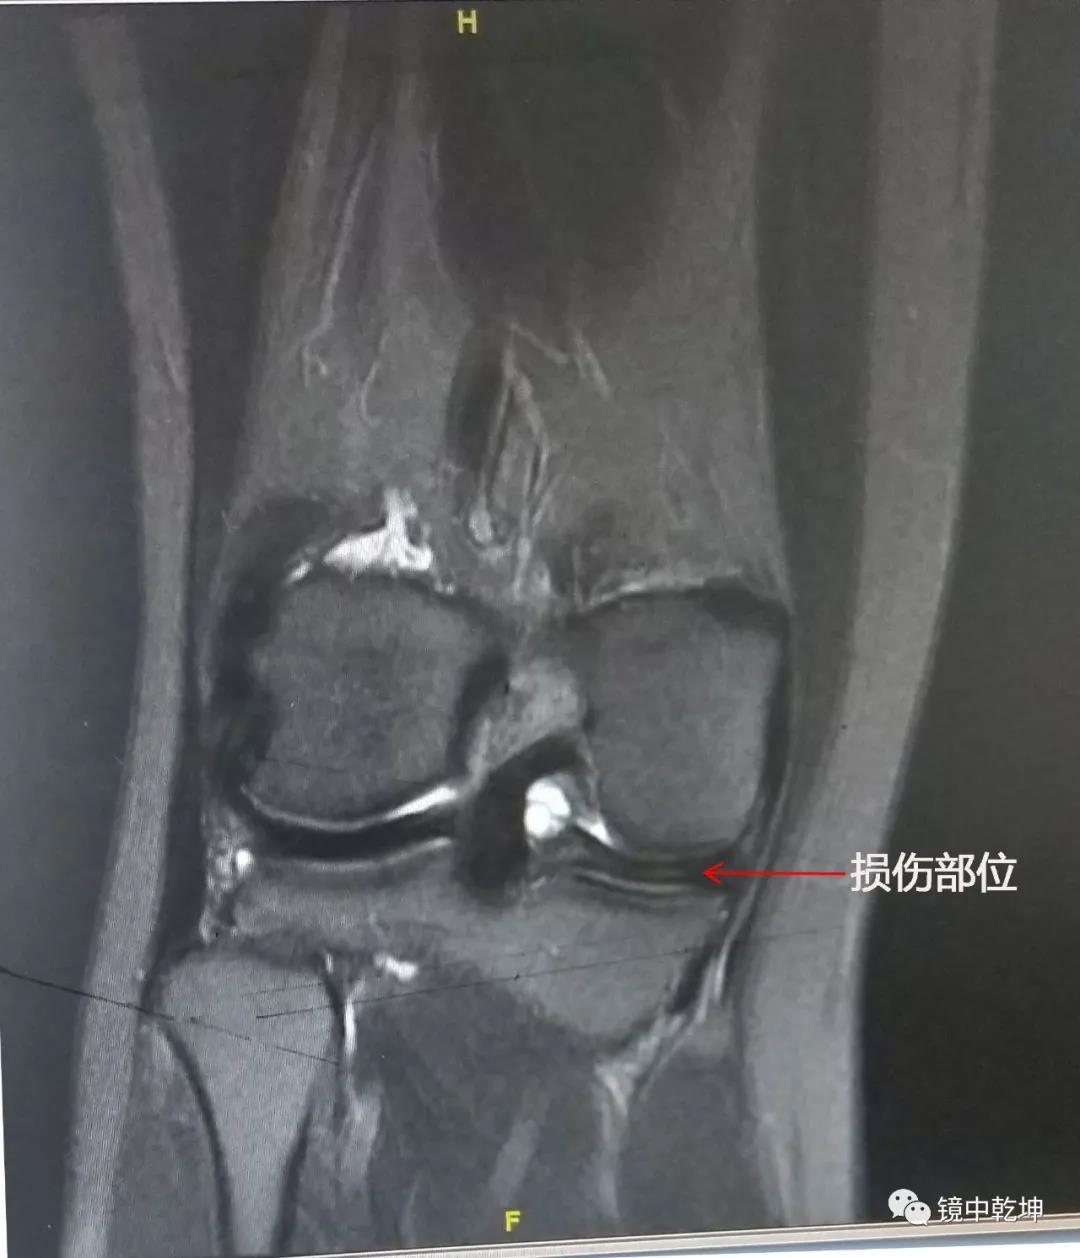

患者陈女士的MRI检查:

南昌大学第二附属医院骨科专家郝亮博士,李晨博士结合陈女士病情,诊断为半月板撕裂伤,并制定了手术方案。